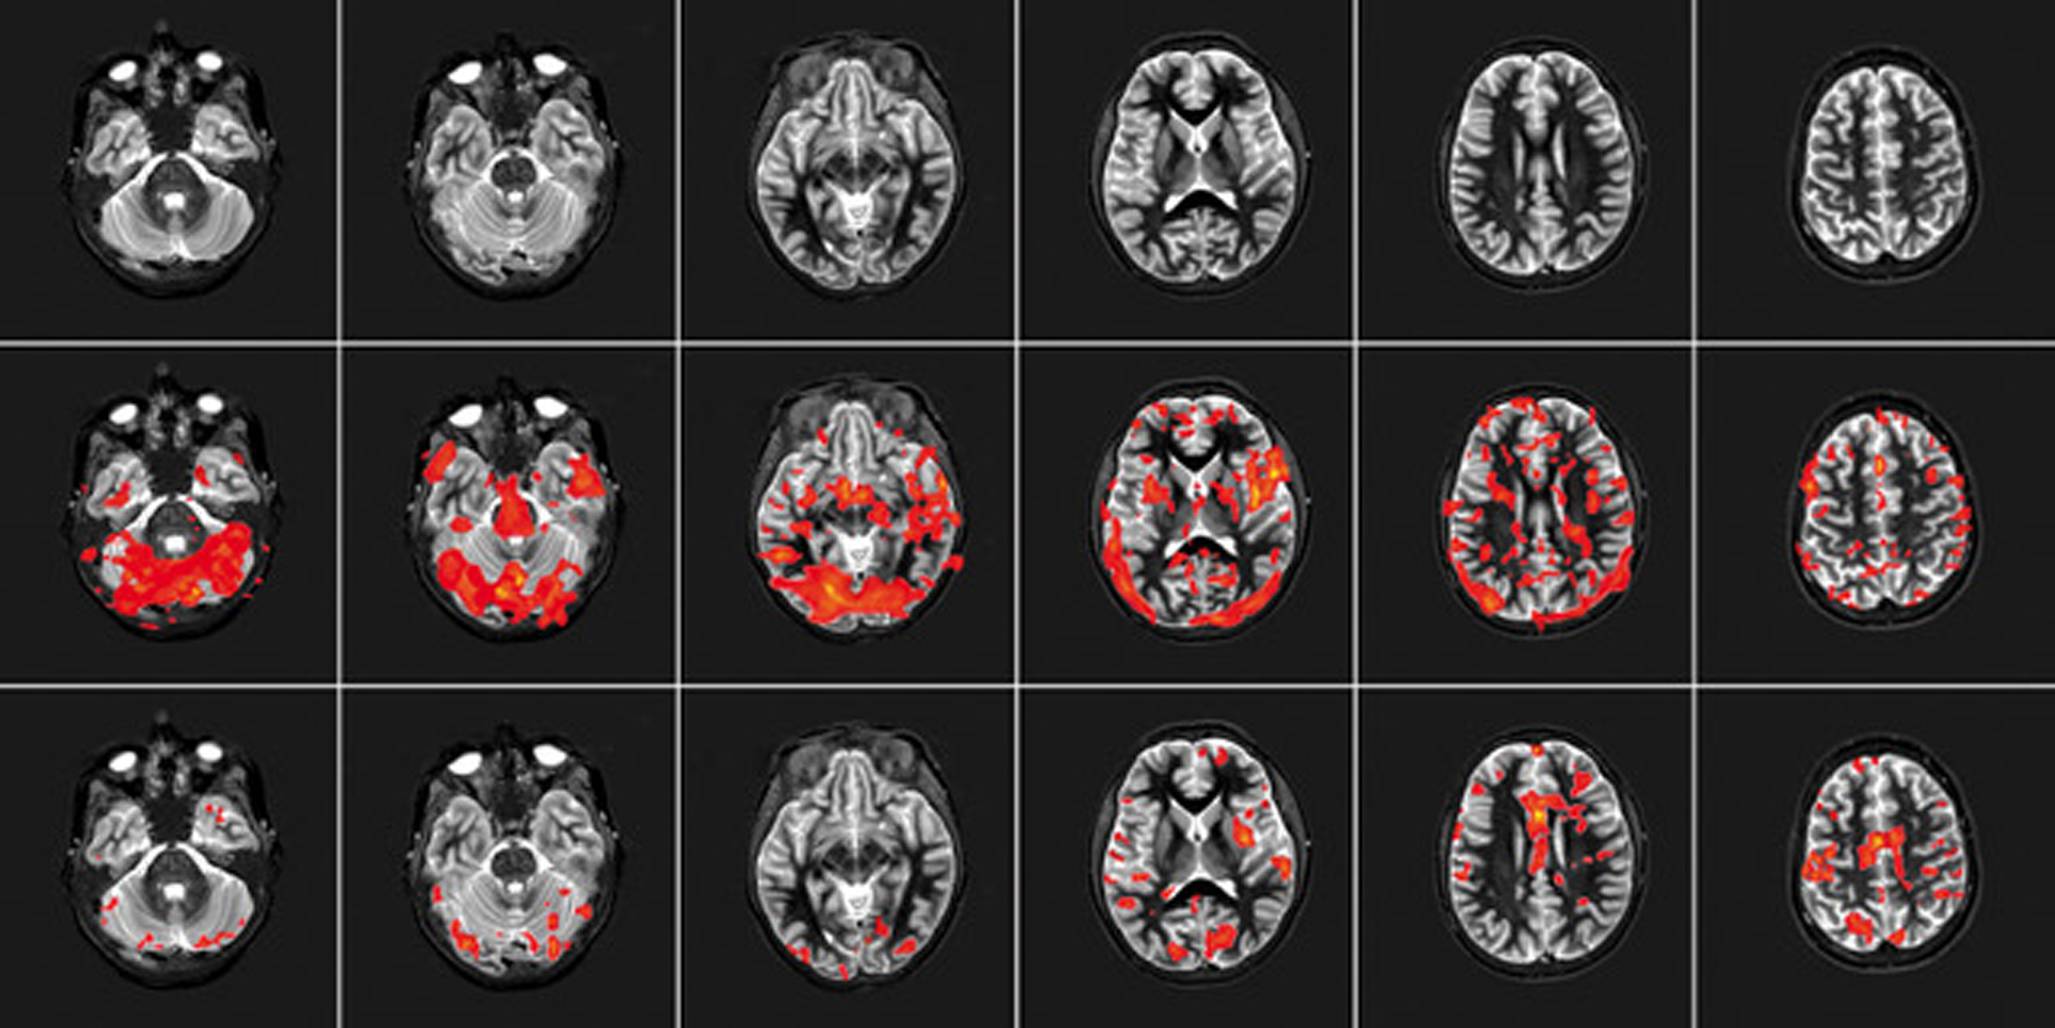

Louw zeigt dieses Umlernen plastisch an einer fMRT einer Schmerzpatientin (Abb. 2).

Abb. 2

Erklärung im Rahmen der Pain-Neuroscience-Education (PNE): Die Schnittbilder in der oberen Reihe zeigen eine entspannte Patientin in der fMRT, die einen beruhigenden Film ansieht. In der mittleren Reihe fMRT-Bilder nachdem die Patientin eine schmerzhafte Bewegung (Beckenkippung bei aktivierter lumbaler Osteochondrose) durchführt. In der unteren Reihe gleiche schmerzhafte Beckenkippung, jedoch nach erfolgter PNE, zeigt deutlich verminderte Aktivierung. Copyright Adrian Louw, mit frdl. Genehmigung, aus [21]

In Kenntnis der vorausgegangenen Entwicklungen der PNE, die natürlich alle für den englischsprachigen Raum entwickelt wurden und auch entsprechende Anpassungen nicht nur sprachlich erforderten, beschlossen die IGOST und die MWE Anfang 2024 ein deutschsprachiges Modul zur Patientenedukation zu entwickeln, unter Berücksichtigung wissenschaftlicher und neurophysiologischer Erkenntnisse. Hierbei wurden insbesondere die bekannten Grafiken modernisiert und auf ein sogenanntes „flat design“ verändert. Zum Teil wurden Originalabbildungen wegen der guten Verwendbarkeit (so auch Abb. 2) in das System übernommen, die Rechte wurden dazu von Adriaan Louw erteilt.

In einem Fallbeispiel konnte gezeigt werden, wie präoperative PNE in der fMRT die Aktivität postinterventionell deutlich senken konnte [21], wie auch in Abb. 2 gezeigt.